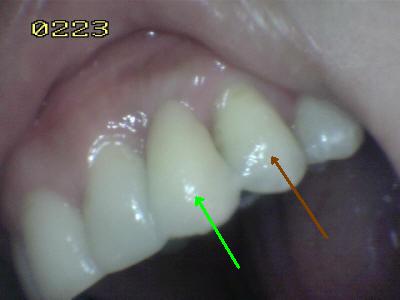

• En la fotografía se muestra el reemplazo del canino, este por lo tanto debe desocluir a los posteriores en el lado de trabajo y balance.

• Observar el aspecto estético, y eliminar los posibles excesos de cemento. (La flecha verde indica cual es el póntico tipo Maryland; la flecha marrón indica el diente natural al cual se ha imitado la tonalidad o matiz)